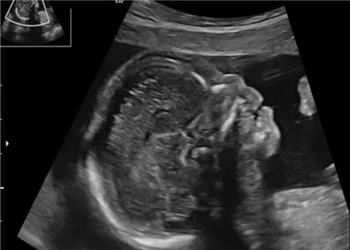

آیا تشخیص زودهنگام «سندرم داون» با شاخص استخوان بینی ممکن است؟

ایران پرسمان - ایسنا /در سالهای اخیر پیشرفتهای تصویربرداری در بارداری به پزشکان امکان داده تا زودتر از گذشته ناهنجاریهای جنینی را تشخیص دهند. یکی از شاخصهایی که ...